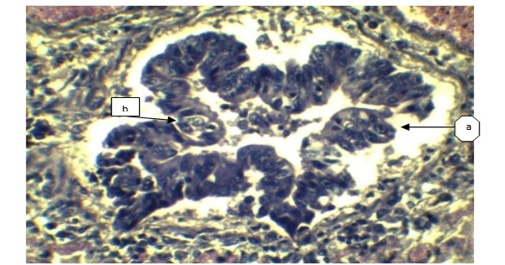

a) Sloughing off surface epithelium of bronchi; b) Necrosis of bronchiolar epithelium. (H&E x 40).